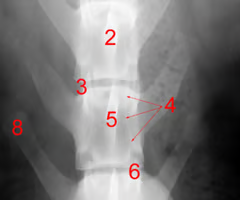

Identify structure 1, 2, 5, 7:

Spinous process

Vertebral body

Vertebral canal

Dorsal laminae

Identify structure 3:

Intervertebral foramen

Identify structure 4:

Pedicle

Identify structure 6:

Articular process

Identify structure 8:

Transvers process